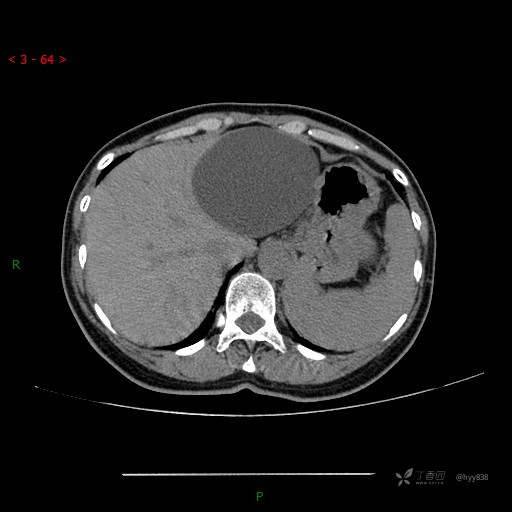

腹部CT平扫